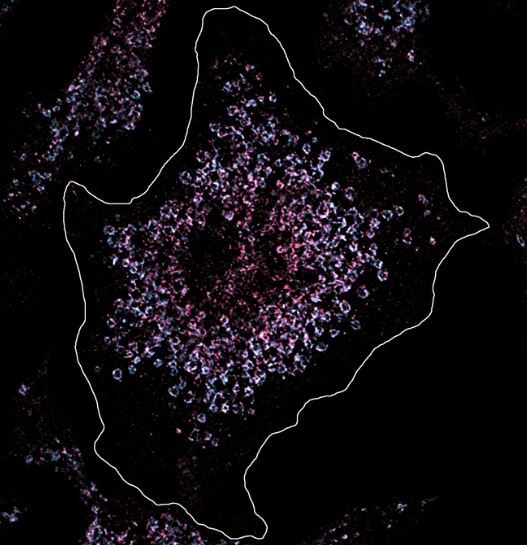

در این سلول ، گیرنده ی 7 رنگ صورتی رنگ شده بود تا مقدار و موقعیت آن را زیر میکروسکوپ تجزیه وتحلیل کند. سلول سالم است و مقدار گیرنده های شبیه به هزینه طبیعی است. وضعیت در سلول های ایمنی بیماران مبتلا به لوپوس متفاوت است که تعداد گیرنده های آن به طور قابل توجهی افزایش یافته است ، به این ترتیب مواد ژنتیکی بدن شناسایی می شود و التهاب مزمن لوپوس ایجاد می شود.